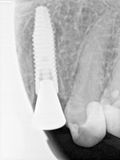

fredlibc | all galleries >> Galleries >> ARumiantsava-immediate 23 > R7.jpg

R7.jpg